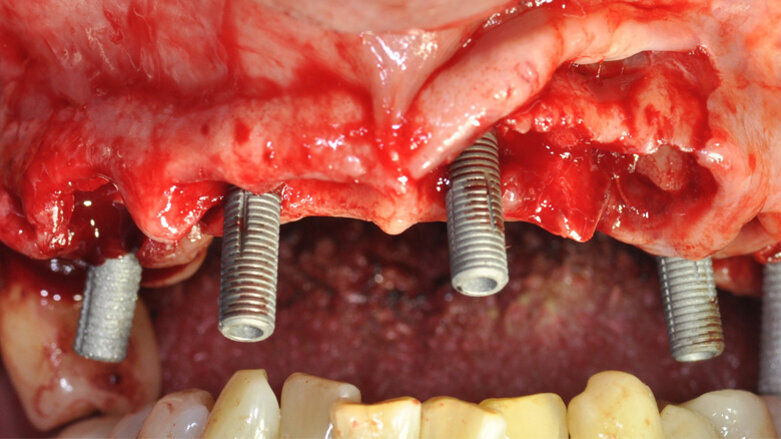

I pazienti considerati eleggibili all’inclusione erano coloro che fossero stati sottoposti a riabilitazione con protesi full-arch a carico immediato con tecnica Flat-one-Bridge (Figg. 1, 2). I pazienti, già al tempo della chirurgia, erano inclusi solo se maggiorenni, complessivamente in salute, condiscendenti alle misure di igiene orale prescritte e alle visite di controllo programmate. I criteri di esclusione erano: presenza di fattori sistemici o locali che avrebbero potuto controindicare la chirurgia, scarsa igiene orale, abitudine al fumo di più di 10 sigarette al giorno, gravidanza, storia di dipendenza e/o abuso di sostanze stupefacenti e/o alcool.

Tutti i pazienti sono stati trattati con tecnica FoB su almeno 5 impianti con superficie Ossean (Intra-Lock) raggiungendo un torque non inferiore a 35 Ncm (Fig. 3). Gli impianti in questione presentano una superficie nano-irruvidita con Calcio e una macro-geometria che ben si adatta al carico immediato15, 16. In particolare, il disegno conico facilita l’ottenimento della stabilità primaria ed è stata associata a una osseointergazione precoce della fixture nelle prime settimane17.

Fig. 3_Foto intra-orale durante il posizionamento degli impianti nell’arcata superiore.